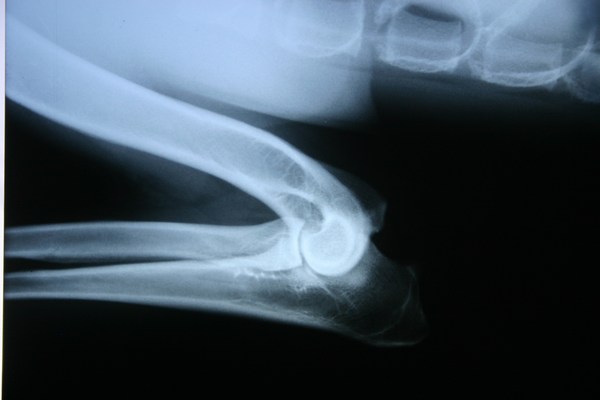

A könyökízületi diszplázia lényege, hogy a könyökízületet alkotó kar csont és két alkar csont egymással érintkező ízületi felszíne nem illeszkedik megfelelően egymáshoz.

Ennek következtében helyenként (a túl szoros illeszkedés következtében) feszülés, más helyen pedig (a túl laza illeszkedés miatt) instabilitás jön létre a diszpláziás könyökízületben. Az illeszkedési hibákból eredően a könyökízületben porcleválások (anconeus és coronoideus leválás), porcdegeneráció (oszteokondró-zis dissecans), porckopásokkal, porcfelrakódásokkal kísért degeneratív ízületi betegség, arthrosis jön létre.

A könyökízületi diszplázia enyhe formájára az enyhe könyökízületi arthrosis jellemző. A súlyos könyökdiszpláziára a könyökízület porcainak leválása (anconeus ill. coronoideus leválás, könyök OCD), nagyfokú könyökízületi inkongruencia (könyökízületi lépcső), valamint súlyos könyök arthrosis jellemző.

Mindemellett észrevehető a könyökízületek duzzanata is. Ezen tünetek észlelésekor haladéktalanul forduljunk állatorvoshoz. Az idős korban jelentkező könyökizületi diszpláziára a pihentetés után kialakuló, visszatérő sántaság jellemző. A könyök diszpláziás kutya könyökízülete duzzadt, nyújtása-hajlítása korlátozott, illetve fájdalmas. A röntgenfelvételen ilyenkor porcleválások, porckopások, valamint porcfelra-kódások láthatók. Súlyos könyök diszplázia esetén fiatal korban minden esetben műtét javasolt. Idős kori könyökdiszplázia esetén gyógyszeres kezelés, esetleg műtéti megoldások javasoltak. Fontos tudni, hogy a fiatal korban nem megoperált, súlyos időskori könyökízületi arthrosis esetén már nem létezik jól használható műtéti megoldás, leginkább csak a gyógyszeres kezelés marad.